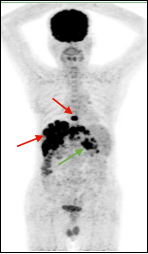

图A绿色箭头示右侧胸膜多发转移,图B红色箭头示结肠肝曲局部管壁稍厚形成软组织灶,糖代谢增高,肠镜证实结肠肝曲腺癌。

图A 图B

A、B两图均为左肺周围型肺癌,病灶大小相似,A未见远处转移病灶,B全身广泛转移,临床分期分别为ⅡB期及ⅣB期,PET/CT不同分期影响临床治疗决策。